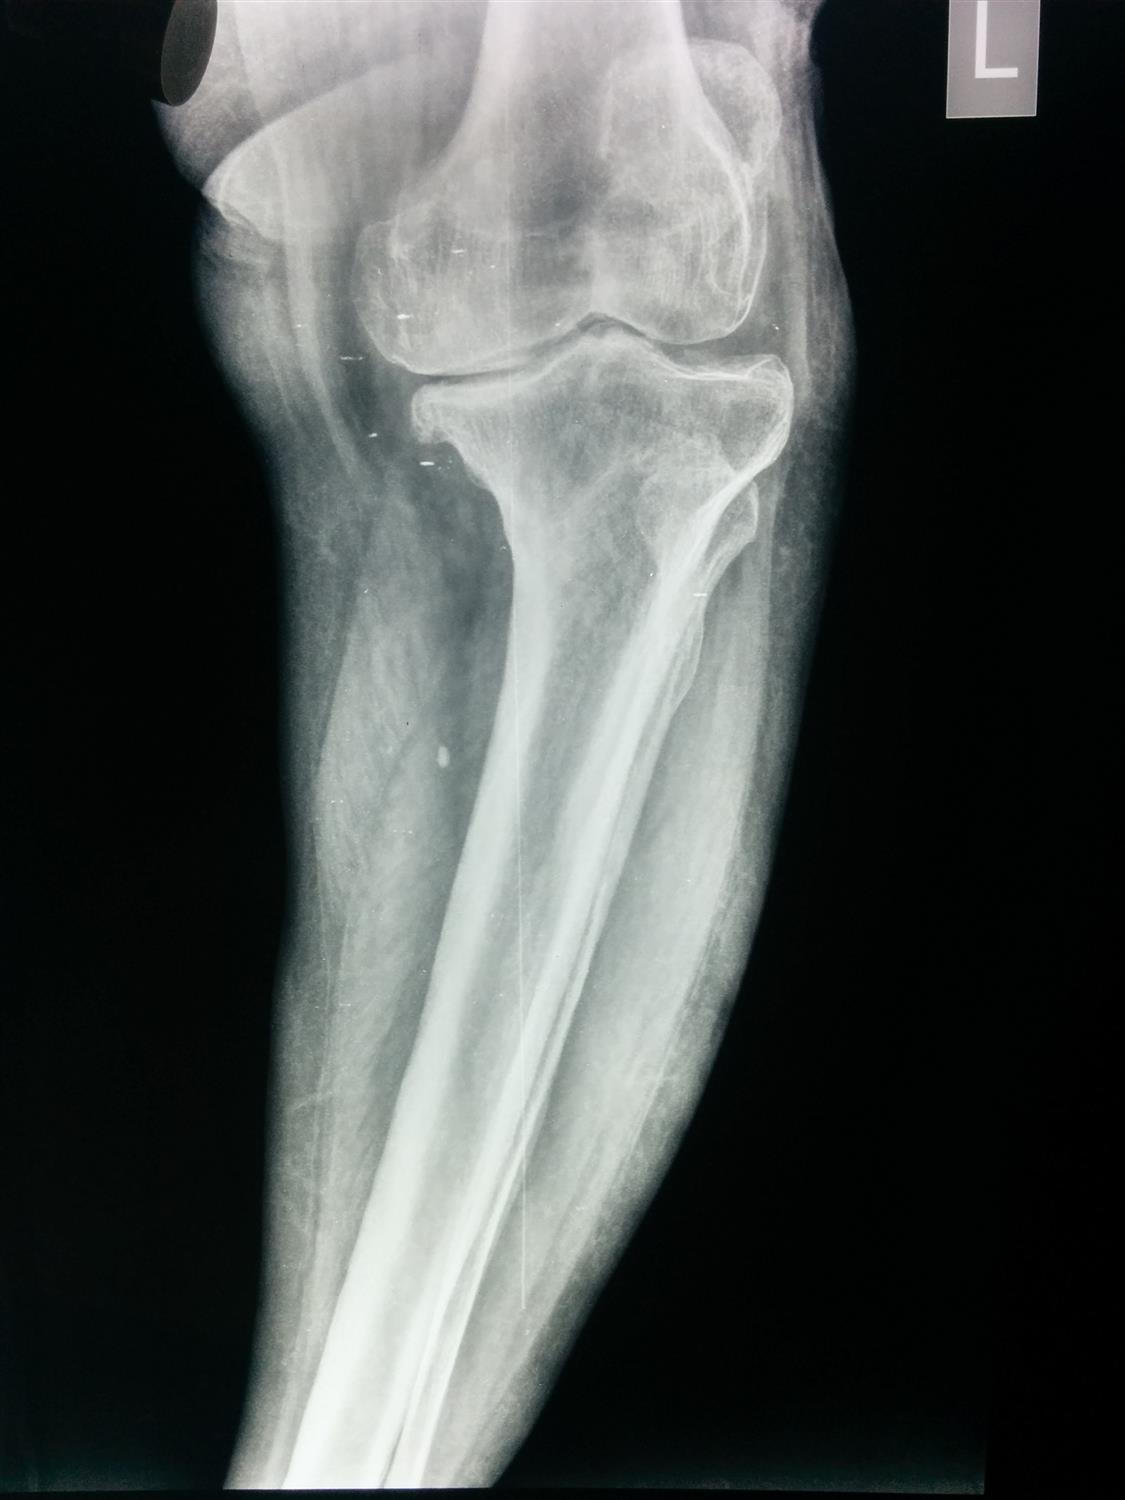

Adult Knee Radiographic Evaluation Recon Orthobullets Knee Balancing Orthobullets This article reviews different techniques to position tka implants, including kinematic alignment, which aims to restore the patient's. Balance flexion and extension gaps by adjustment of polyethylene bearing thicknesss Soft tissue balancing during total knee arthroplasty (tka) is an important step for optimizing the outcome of the procedure and providing. We compared knee arthroplasties performed using either a measured resection. Knee Balancing Orthobullets.

Adult Knee Radiographic Views Trauma Orthobullets Knee Balancing Orthobullets Measured resection is a total knee arthroplasty (tka) technique that relies on bony landmarks to set component placement and adapts the soft tissues to the chosen implant position. Soft tissue balancing during total knee arthroplasty (tka) is an important step for optimizing the outcome of the procedure and providing. We compared knee arthroplasties performed using either a measured resection or. Knee Balancing Orthobullets.